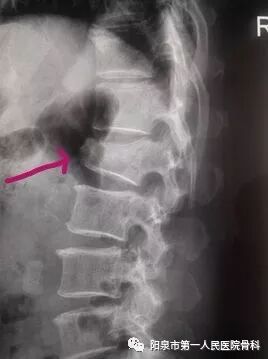

在X线上的典型表现为椎体呈前窄后宽形状如下图红色箭头所示。

椎体成型需要哪些器材椎体成形术概述_https://www.jmylbn.com_新闻资讯_第12张

下图红箭头所示为椎体因肿瘤而被破坏的表现。此时患者多会表现持续性加重的背部疼痛,严重影响日常活动。

椎体成型需要哪些器材椎体成形术概述_https://www.jmylbn.com_新闻资讯_第14张